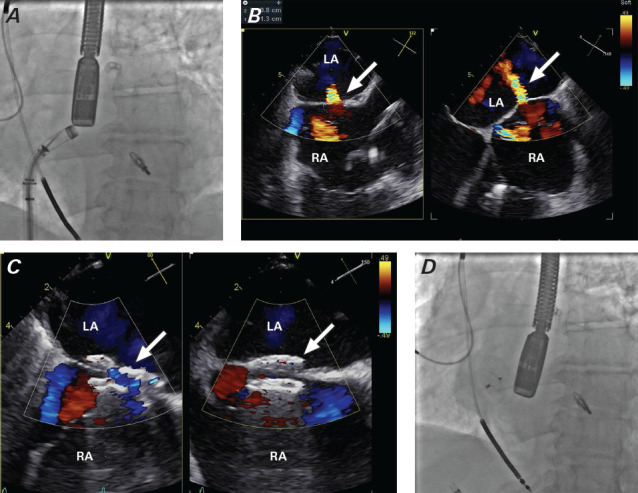

The evolution of percutaneous procedures that use transseptal puncture to treat left-sided structural heart disease has led to the emergence of iatrogenic atrial septal defects as a potential complication. These defects can result in hemodynamic decompensation and worsening clinical outcomes. Some iatrogenic atrial septal defects require immediate closure, others do not. This case report presents 2 patients who underwent transcatheter edge-to-edge mitral valve repair with transseptal puncture and required iatrogenic atrial septal defect closure (1 immediate and 1 delayed). The goal of this report is to highlight iatrogenic atrial septal defect assessment and the possible need for closure after transseptal puncture.